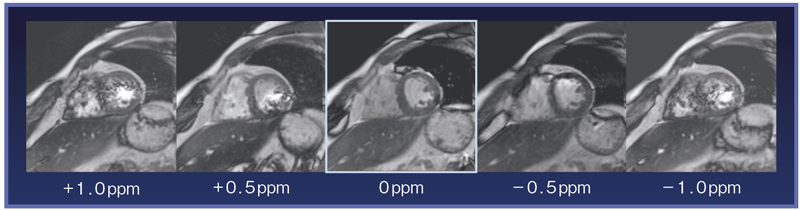

3テスラ装置による心臓mri より早く質の高い検査を目指して 横山 健一 杏林大学医学部放射線医学教室講師 Jrc2012 合同企画 産学連携セミナー1 東芝メディカルシステムズ株式会社 Innavi Suite

Vantage Titan 3t によるcardiac Imaging 東芝メディカルシステムズ株式会社 Innavi Suite

2013 226388号 磁気共鳴イメージング装置及び磁気共鳴イメージング方法 Astamuse